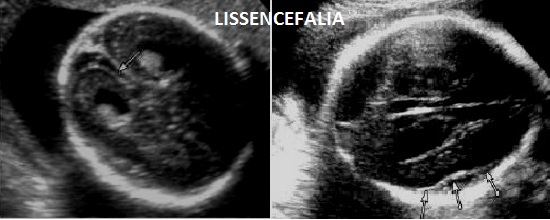

La Sindrome di Norman-Roberts o Sindrome lissencefalica tipo Norman-Roberts è un sottotipo della lissencefalia tipo 1 dovuta a mutazione del gene RELN che mappa in 7q22 ed è trasmessa con carattere autosomico recessivo.

E' caratterizzata dall'associazione lissencefalia tipo 1 ed anomalie cranio facciali consistenti in microcefalia, ipertelorismo, fronte alta, sella nasale prominente. Gli emisferi cerebrali mostrano una superficie liscia con fessure Silviane mal definite e il fallimento della differenziazione dell'insula.